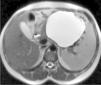

Mujer de 36 años con tumoración quística pancreática y trombopenia